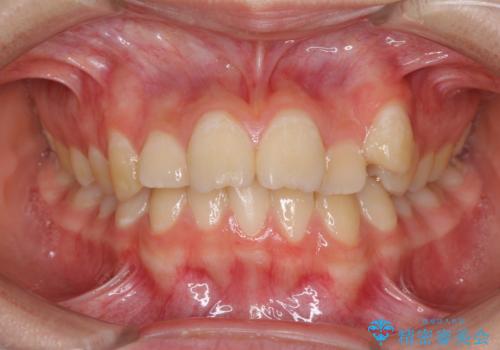

上下前歯の前歯と腫れやすい歯肉 インビザライン矯正で改善